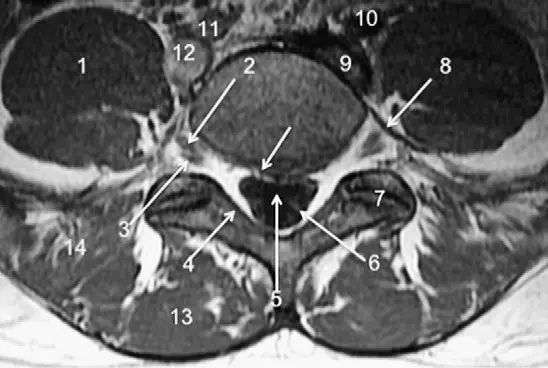

脊柱的MRI解剖

(1)前柱,包括脊柱前纵韧带、椎体及椎间盘的前2/3部分;

(2)中柱,由椎体及椎间盘后1/3和后纵韧带组成;中柱损伤者属于不稳定性骨折。

(3)后柱,由椎弓、椎板。附件及黄韧带、棘间、棘上韧带组成。